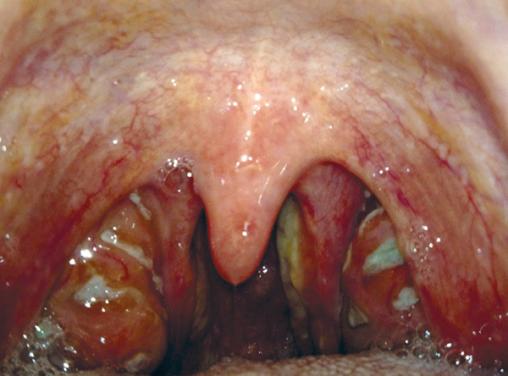

Angine érythémato-pultacée